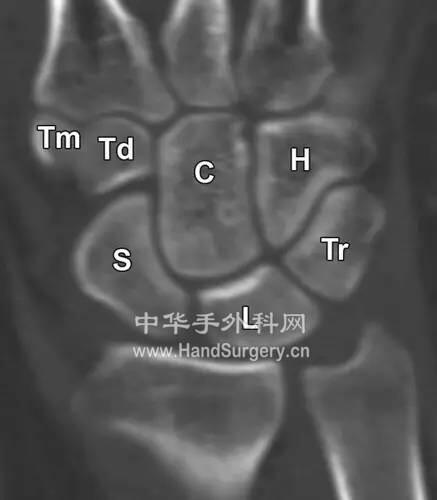

腕关节Gilula线

楼主| 发表于 2020-5-10 23:47:50 | 显示全部楼层

92750465_2.jpg

92750465_3.jpg